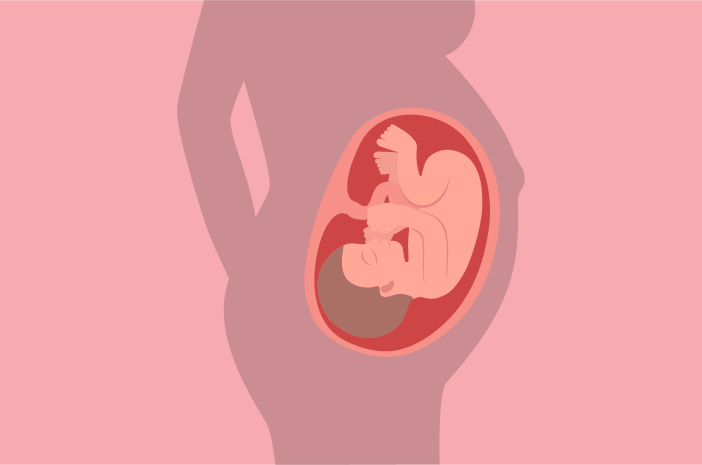

Hamil 36 Minggu Sejauh Apa Perkembangan Janin Anda

Hamil 36 Minggu Sejauh Apa Perkembangan Janin Anda

Kehamilan Minggu Ke 36 Popmama Com

Kehamilan Minggu Ke 36 Popmama Com

Perhatikan Hal Hal Berikut Saat Perkembangan Janin Usia 36 Minggu Prenagen

Perhatikan Hal Hal Berikut Saat Perkembangan Janin Usia 36 Minggu Prenagen

Hamil 36 Minggu Sejauh Apa Perkembangan Janin Anda

Hamil 36 Minggu Sejauh Apa Perkembangan Janin Anda

Perkembangan Janin 36 Minggu Panduan Untuk Ibu Hamil

Perkembangan Janin 36 Minggu Panduan Untuk Ibu Hamil